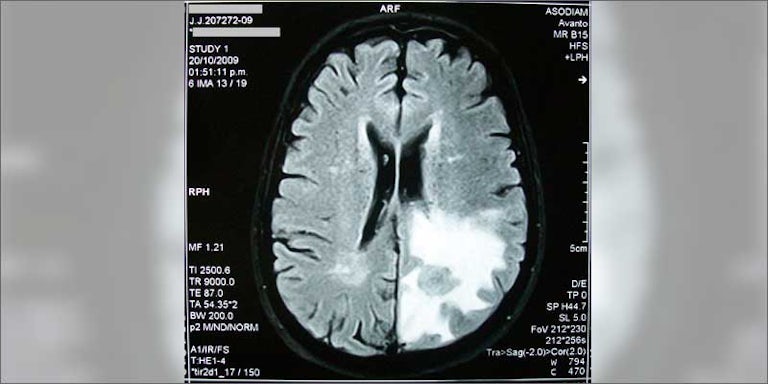

The team, led by Professors Guillermo Velasco and Manuel Guzman, are experimenting cannabinoid treatment’s ability to kill glioma cells. Gliomas make up 80% of all malignant brain cancers. In fact, it’s one amongst the foremost aggressive sorts of cancer out there. Once a glioblastoma reaches stage 4, the average life expectancy is less than two years.

Back in the early 2000s, Dr Velasco and his team had a discovery. They used extracted THC to glioblastoma cells cultured outside of the body. THC is the main psychoactive compound in cannabis. What happened shocked researchers around the world. The tumour cells stopped growing. Later on, tumour cells actually began to die.

THC kills glioblastoma cells in a couple of ways. THC and other cannabinoids cut off the tumour’s blood supply and cause cancer cells to commit suicide.